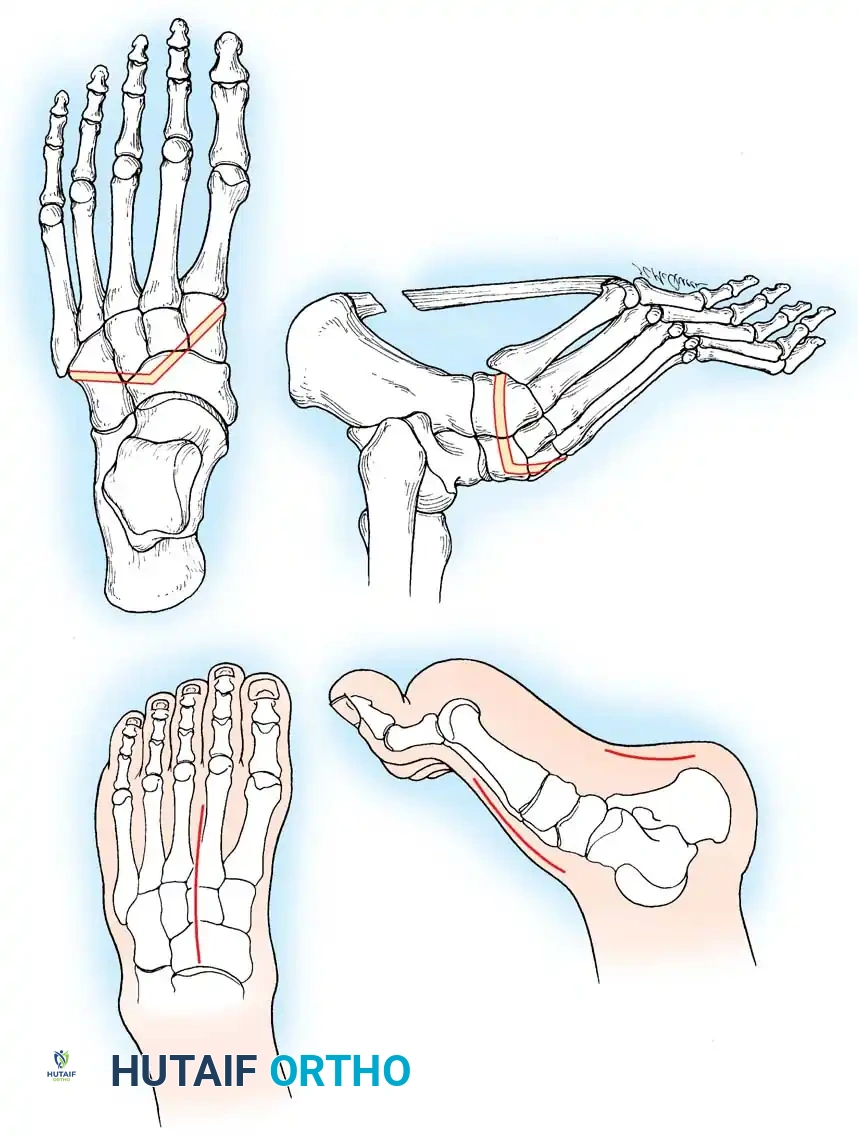

1. Forefoot Valgus: The unopposed pull of the strong peroneus longus against a weak tibialis anterior forcefully plantarflexes the first ray, causing fixed pronation of the forefoot (forefoot valgus).

2. Hindfoot Varus: With weakness of the peroneus brevis, the strong tibialis posterior exacerbates forefoot equinus and forcefully inverts the midtarsal joints.

As the first ray becomes rigidly plantarflexed, it acts as a kickstand. When the foot strikes the ground, the plantarflexed first metatarsal forces the hindfoot into a compensatory varus position. Over time, the plantar fascia contracts, and what began as a flexible, forefoot-driven hindfoot varus becomes a rigid, fixed bony deformity.

* Meary’s Angle (Talus-First Metatarsal Angle): Normally 0 degrees. In a cavus foot, the angle is convex upward (apex dorsal), indicating midfoot/forefoot equinus.

* Calcaneal Pitch: Normally 15 to 20 degrees. In a cavus foot, it is significantly increased (>30 degrees).

* Hibbs Angle: The angle between the longitudinal axis of the calcaneus and the first metatarsal. It approaches 90 degrees in severe cavus (normal is ~140 degrees).

* Talonavicular Coverage: Assessed on the AP view to quantify midfoot adduction.